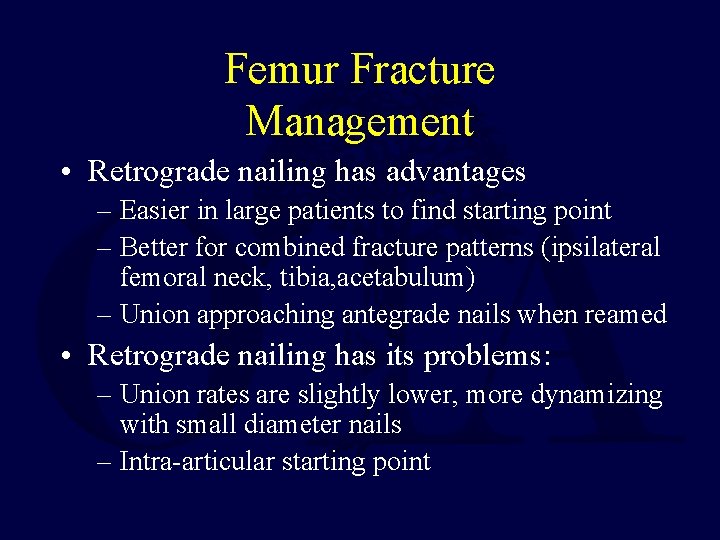

Femur Fracture Management • Retrograde nailing has advantages – Easier in large patients to find starting point – Better for combined fracture patterns (ipsilateral femoral neck, tibia, acetabulum) – Union approaching antegrade nails when reamed • Retrograde nailing has its problems: – Union rates are slightly lower, more dynamizing with small diameter nails – Intra-articular starting point